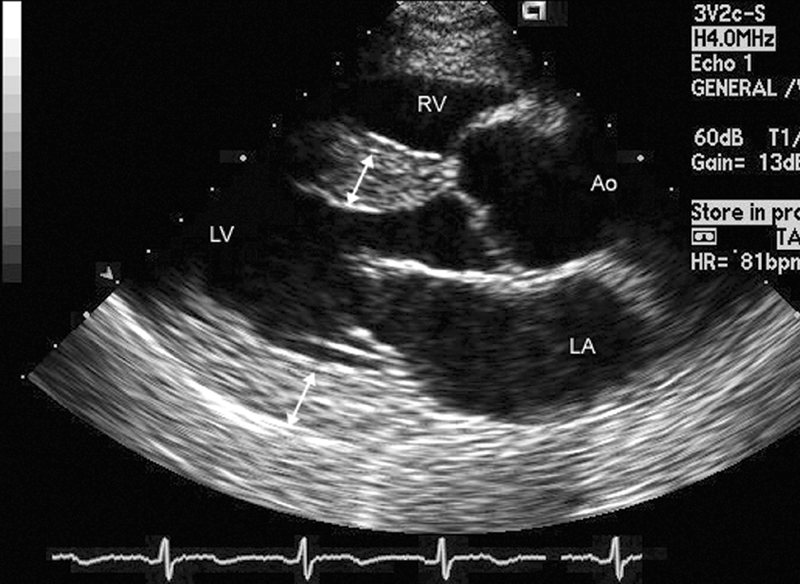

فحوصات تشخيصية لبعض امراض القلب والشرايين التاجية